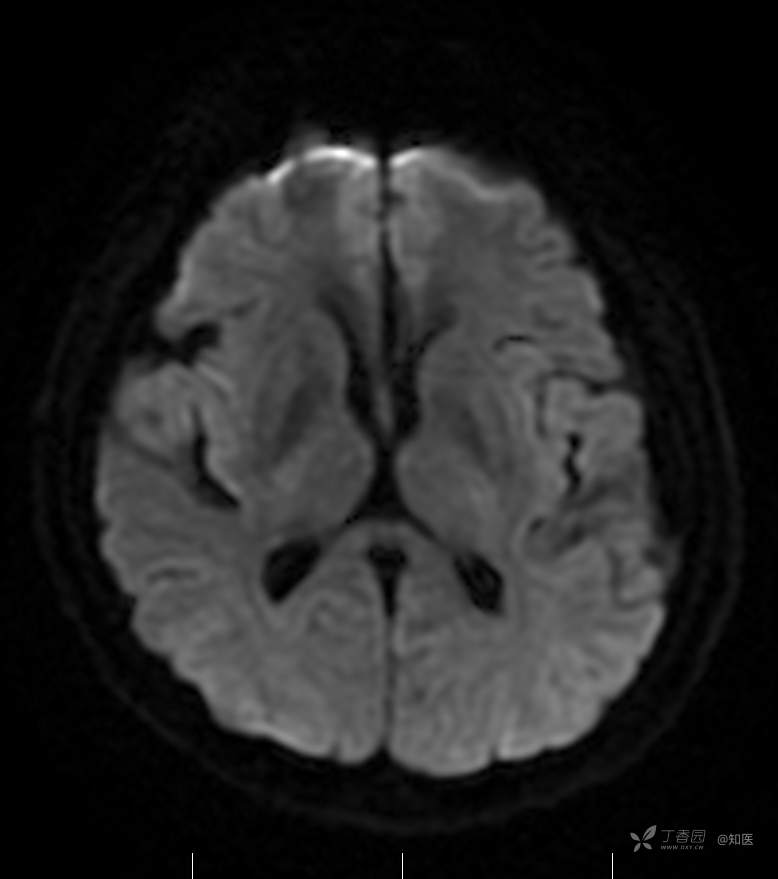

2021-6-15 DWI

2021-06-16日晨查房,患者自觉入院治疗后肢体无力症状较前稍改善,仍有活动后气短,余未诉特殊不适。ALSFRS-R评分:44分(单项均大于等于2分)。血压:123/63mmHg。神经系统查体:GCS 15分,右利手,查体合作,问答切题,粗测智能基本正常。额纹对称,双眼闭目紧,双侧瞳孔等大等圆,直径约3.0mm,对光反射灵敏,眼球运动自如,无眼震,双侧鼻唇沟对称等深,口角无歪斜。悬雍垂居中,双侧软腭抬举良好,咽反射灵敏、转颈、耸肩均一致有力。颈屈肌、颈伸肌力量5级。伸舌居中,无舌肌纤颤及萎缩。双侧岗上肌、岗下肌可见萎缩;双侧三角肌可见偶发肉跳、肌力5级,左侧肱二头肌肌力4+级、右侧4-级,双侧肱三头肌肌力4+级;双手握力可,双手大小鱼际肌及第一骨间肌可见萎缩,左侧明显,左侧手腕背伸力量4级、右侧4+级,双侧拇短展肌肌力4-级,双侧示指伸肌肌力3级,左侧指总伸肌肌力4级、右侧4-级,双侧小指展肌肌力4-级。双上肢肌张力对称减低。左侧肱二头肌反射迟钝、右侧未引出,双侧桡骨膜反射及肱三头肌反射未引出。左侧胸大肌反射阳性、右侧未引出,双侧Rossolimo征阳性、Hoffmann征阴性,下颌反射阴性。腹壁反射未引出。双下肢可见肌肉萎缩,以左侧明显;左侧髂腰肌肌力4级、右侧4-级,双侧股四头肌肌力5级,双足背伸力量3级,左足跖屈力量4级、右足4+级。双下肢肌张力对称基本正常。双侧膝腱反射、跟腱反射迟钝,双侧跖反射消失,双侧巴氏征未引出。右侧大腿外侧肌肉活检瘢痕周围浅感觉缺失,余肢体及躯干深浅感觉正常,共济运动对称正常。颈软,无抵抗,双侧布氏征及克氏征均阴性。辅助检查:微量元素(钙、镁、铁、铜、锌),微量元素测定(铅,镉)[复][2021-6-16 16:11:07]:钙1.19mmol/l;铁9.00mmol/L。急诊电解质七项[复][2021-6-16 10:41:41]:钾3.55mmol/L。血细胞分析+五分类[2021-6-16 9:57:17]:淋巴细胞百分比19.5%。[头颅,扩散成像(DWI)][头颅,磁敏感成像(SWI)][头颅,水抑制成像(FLAIR)][2021-6-16 18:10:50]:1.多发腔梗,脑白质脱髓鞘,脑萎缩。2.DWI:脑实质内未见明显高信号。3.磁敏感成像脑实质内未见明显异常信号灶。MMSE:26分(高中文化水平)。MoCA:23分。ADL评分:14分。ECAS评分:96分(ALS特异67分、ALS非特异29分)。肌电图:提示颈髓、腰髓、胸髓和延髓支配肌肉可见活动期神经源性损害,颈髓和腰髓支配肌肉同时可见慢性期神经源性损害;提示脊髓前角细胞损害可能,请结合临床。心电图大致正常。外送基因检查:TBK1基因杂合子,提示额颞叶痴呆和(或)肌萎缩性侧索硬化症4型。二线主治医师查看患者后示:1.患者基因检查结果显示TBK1基因杂合子,提示额颞叶痴呆和(或)肌萎缩侧索硬化症4型,结合外院影像学检查可见额颞叶萎缩明显,来院后复查头颅FLAIR+DWI+SWI亦提示脑萎缩,量表评估提示认知功能稍减退,ECAS评分基本正常。综上,修正诊断:肌萎缩侧索硬化症(ALS) 额颞叶变性 低钾血症 高血压2级(高危) 多发腔隙性脑梗死。因TBK1基因引起的额颞叶痴呆和(或)肌萎缩侧索硬化症为常染色体显性遗传,患者父亲已逝,母亲健在,诉无明显认知功能障碍或肌肉萎缩等表现,建议患者母亲抽血送检,进一步明确致病基因来源,必要时患者子女也可行基因检查进一步明确。2.患者目前诊断基本明确,根据文献报道,合并FTD的ALS患者整体生存周期较短(约19个月),目前患者发病已1年余,应充分与患者家属沟通病情,告知疾病预后及生存周期情况,同时建议开始口服利鲁唑片,延缓疾病进展。余治疗方案暂不予调整。密观病情变化,遵嘱执行。

2021-06-18出院总结: 卫某某,男,60岁,以“四肢僵硬1年,加重伴无力半年”之主诉入院。查体:生命体征平稳,心肺腹查体无明显异常。神经系统查体:GCS 15分,右利手,查体合作,问答切题,粗测智能基本正常。额纹对称,双眼闭目紧,双侧瞳孔等大等圆,直径约3.0mm,对光反射灵敏,眼球运动自如,无眼震,双侧鼻唇沟对称等深,口角无歪斜。悬雍垂居中,双侧软腭抬举良好,咽反射灵敏、转颈、耸肩均一致有力。颈屈肌、颈伸肌力量5级。伸舌居中,无舌肌纤颤及萎缩。左侧肱二头肌肌力4+级、右侧肱二头肌及双侧三角肌肱三头肌肌力5级;左手大小鱼际肌可见萎缩,左手握2指松、右手握力可,左手拇短展肌、示指伸肌、指总伸肌及抬腕力量3级,右手拇短展肌、示指伸肌、指总伸肌及抬腕力量4-级。双上肢肱二头肌反射、肱三头肌反射、桡骨膜反射均对称减低;双侧Hoffmann征、Rossolimo征、胸大肌反射及掌颏反射阴性,下颌反射阴性。双侧上、中、下腹壁反射可引出。左侧髂腰肌肌力4-级、右侧髂腰肌肌力4级,双侧股四头肌肌力5-级;右足背伸力量3级、左足背伸力量2级,双足跖屈力量5级。双下肢膝腱反射、跟腱反射对称减低;双侧膝阵挛、踝阵挛未引出。双侧巴氏征、Chaddock征均未引出。右侧大腿外侧肌肉活检处周围浅感觉减退,余四肢及躯干部深浅感觉正常,共济运动对称正常。颈软,无抵抗,双侧布氏征及克氏征均阴性。辅助检查:肌电图(2021-05-08,某军医大学附属医院):神经源性损害(颈段、腰骶段受累,胸段可疑;重复神经电刺激(低频、高频)可见左腋神经递减现象。 肌肉活检(2021-05-18,某军医大学附属医院):(右股四头肌)考虑神经源性损害,建议结合临床除外运动神经元病等。入院诊断:1.肢体无力:肌萎缩侧索硬化症(ALS);2.高血压1级(中危)。入院后查血清蛋白电泳:α2-球蛋白6.50%。凝血六项:血浆凝血酶原时间比值0.93;凝血酶原国际标准化比值0.93。贫血因子三项:维生素B12>1476.00pmol/L。平诊肝功十三项+平诊心肌酶谱五项+血同型半胱氨酸测定+平诊血脂八项+平诊肾功七项+平诊电解质八项:尿素3.05mmol/L;肌酐49umol/L;钾3.15mmol/L;高密度脂蛋白0.99mmol/L;载脂蛋白A1.131g/L;脂蛋白(a)333mg/L;肌酸激酶420U/L;总胆红素22.1umol/L;直接胆红素5.4umol/L。微量元素(钙、镁、铁、铜、锌),微量元素测定(铅,镉):钙1.19mmol/l;铁9.00mmol/L。急诊电解质七项:钾3.55mmol/L。血细胞分析+五分类:淋巴细胞百分比19.5%。[头颅,扩散成像(DWI)][头颅,磁敏感成像(SWI)][头颅,水抑制成像(FLAIR)]:1.多发腔梗,脑白质脱髓鞘,脑萎缩。2.DWI:脑实质内未见明显高信号。3.磁敏感成像脑实质内未见明显异常信号灶。MMSE:26分(高中文化水平)。MoCA:23分。ADL评分:14分。肌电图:提示颈髓、腰髓、胸髓和延髓支配肌肉可见活动期神经源性损害,颈髓和腰髓支配肌肉同时可见慢性期神经源性损害;提示脊髓前角细胞损害可能。血尿粪常规、免疫八项、风湿三项、血沉、传染指标、血同型半胱氨酸、糖化血红蛋白等未见明显异常。心电图、肺通气功能大致正常。住院期间给予营养神经、清除氧自由基等对症支持治疗。现患者诊断基本明确,生命体征平稳,一般情况良好,可予今日出院。出院诊断:1.肌萎缩侧索硬化症(ALS);2.额颞叶变性;3.低钾血症;4.高血压2级(高危);5.多发腔隙性脑梗死。出院医嘱:1.注意休息,加强营养,低盐、高蛋白高纤维素饮食,注意休息,适当锻炼,避免剧烈运动及重体力劳动。2.出院继续口服药物:甲钴胺 500ug/次,3次/日;辅酶Q10 10mg/次,3次/日;维生素E 100mg/次,2次/日;美金刚 10mg/次,1次/日;利鲁唑片,50mg/次,2次/日,与餐间隔1.5-2小时。3.出院继续用依达拉奉(必存)60mg+0.9%氯化钠 200ml,静滴,1次/日(首疗程14天,后每疗程10天,间隔20天,共使用6个疗程)。4.1月后门诊复查血常规、肝肾功能、电解质功能;3月后我科门诊再次复诊。5.不适随诊。